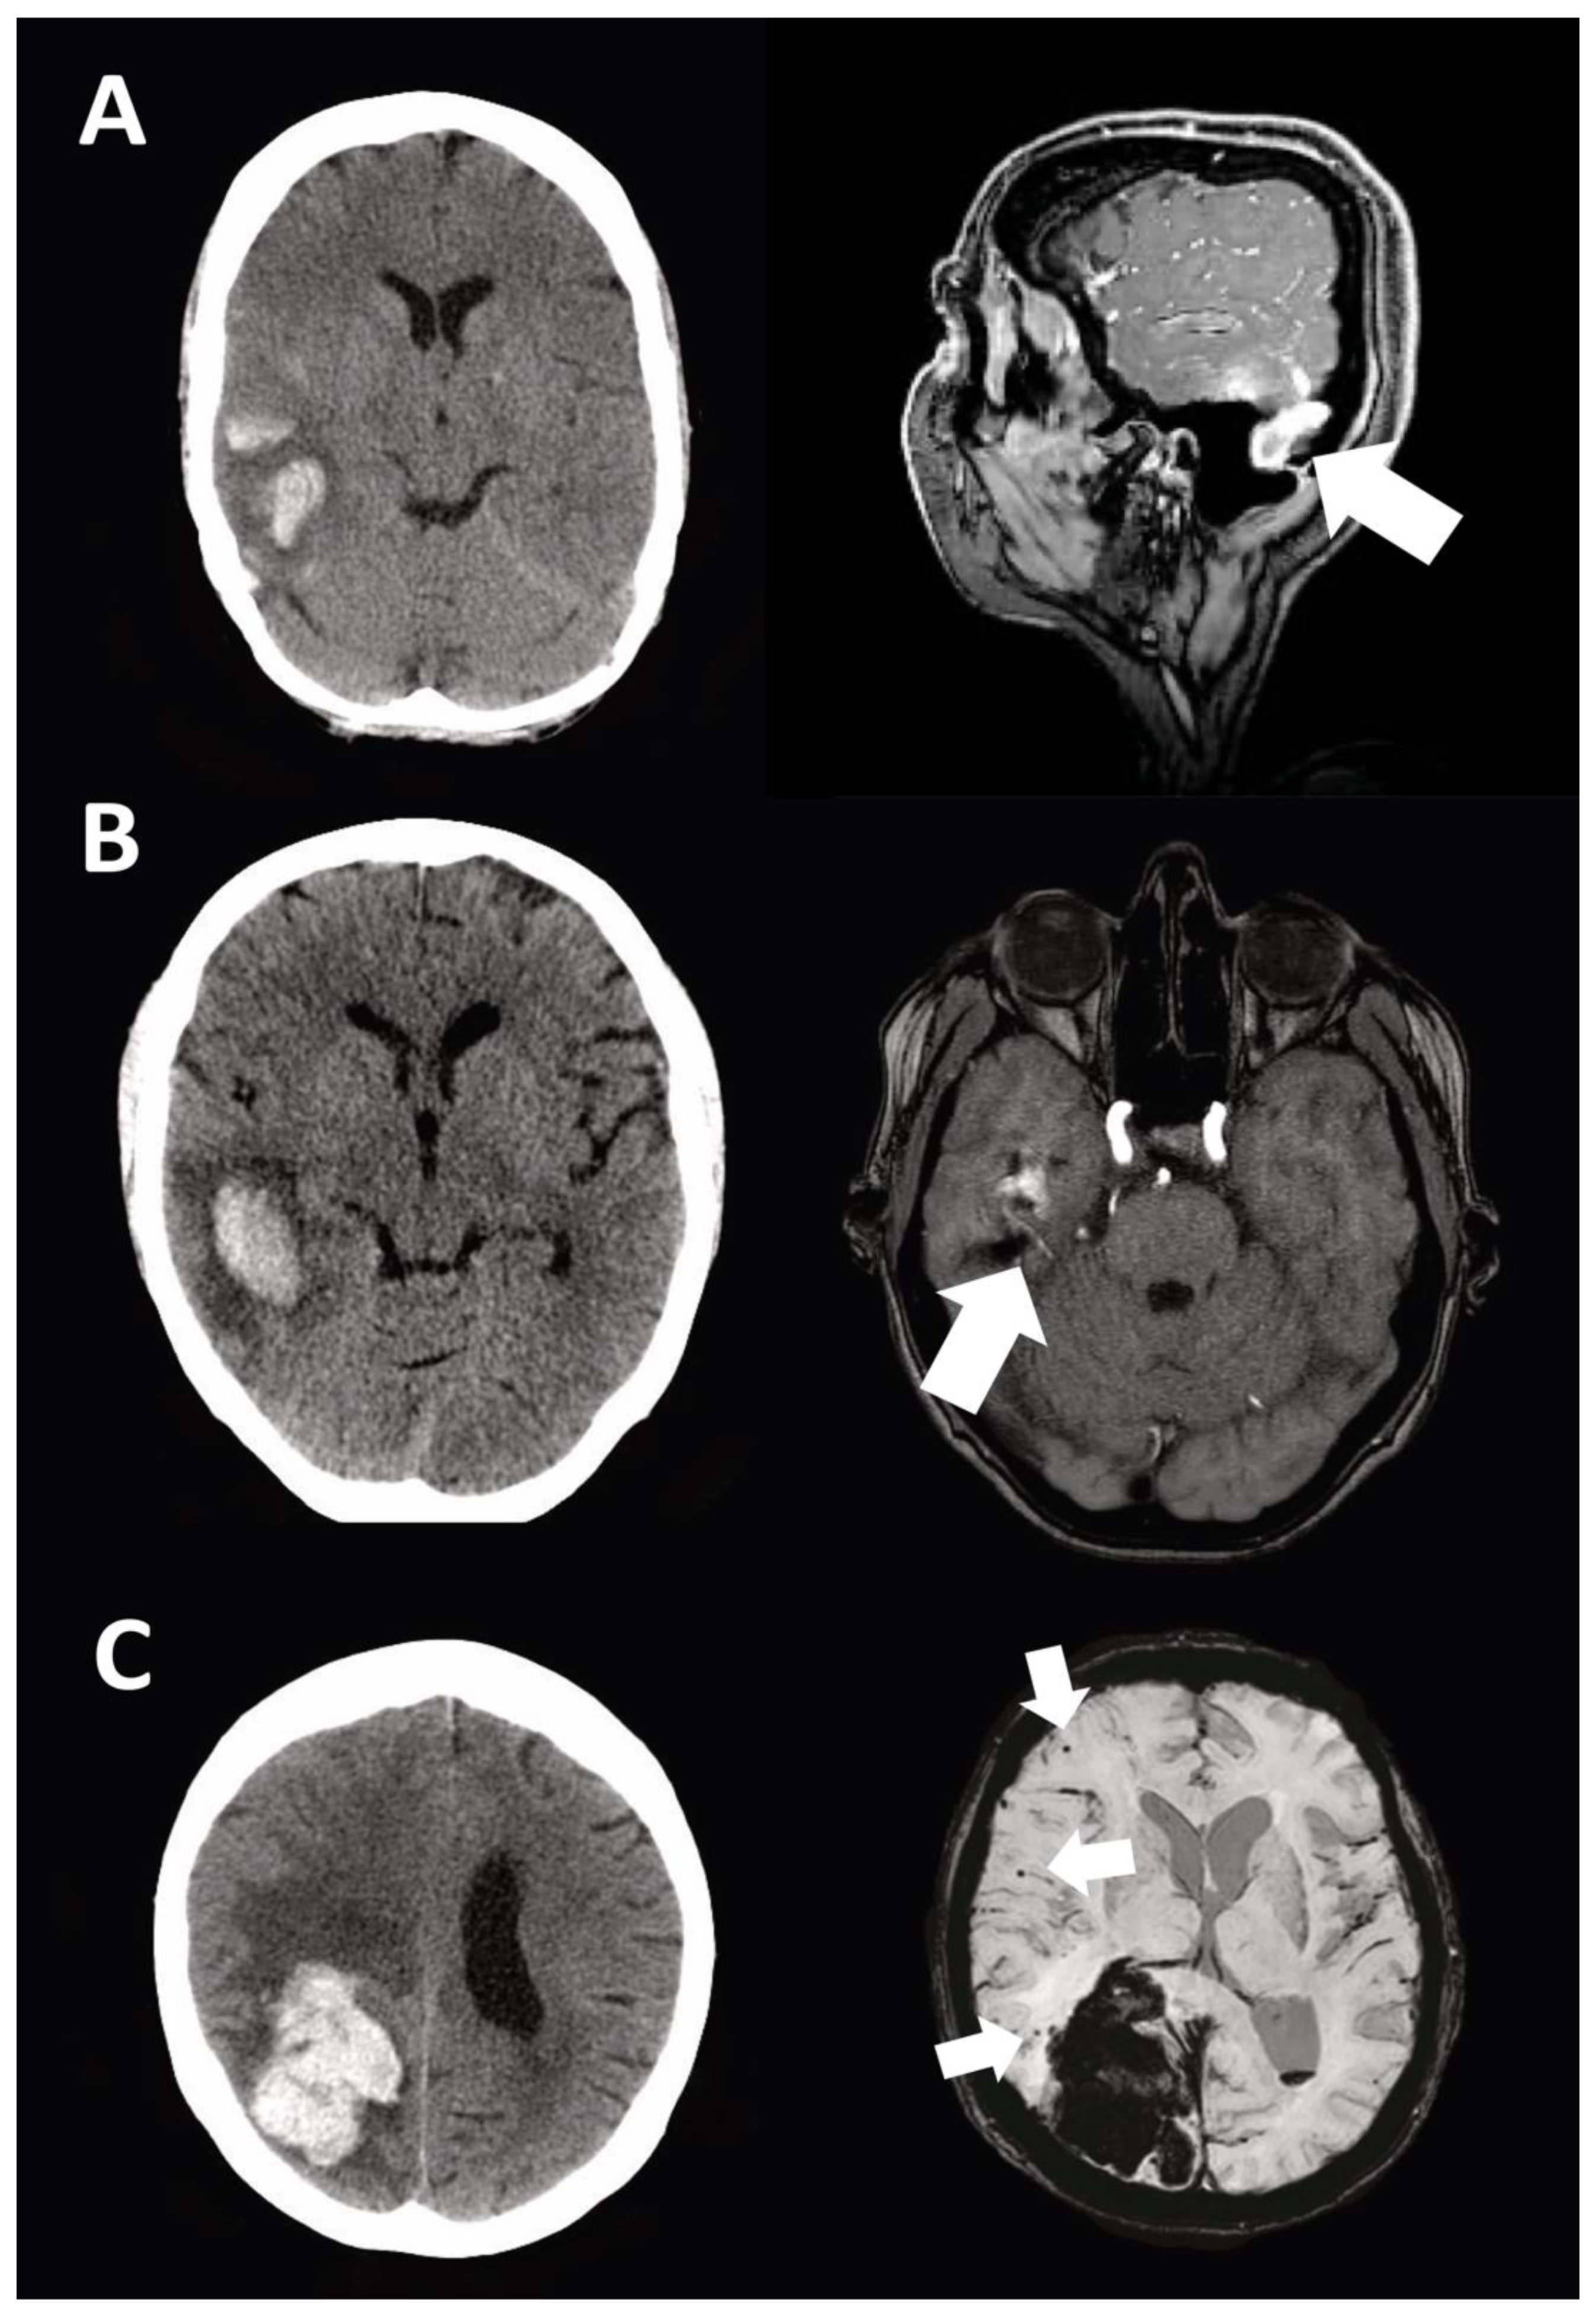

| Macrovascular disease-related ICH | 14 (27%) |

| Ruptured intracranial aneurysm | 7 (13%) |

| Ruptured BAVM | 2 (4%) |

| Ruptured DAVF | 2 (4%) |

| Acute sinus venous thrombosis | 2 (4%) |

| Cerebral cavernous malformation | 1 (2%) |